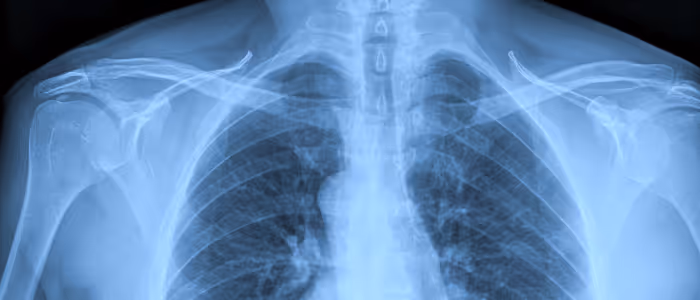

Researchers from the Universidade Federal do Ceará, Instituto Federal do Ceará and Universidade de Fortaleza (all Fortaleza, Brazil) report on the potential for the use of x-ray images combined with artificial intelligence as a tool for the automatic detection of COVID-19.

Using 194 chest X-ray images of patients diagnosed with COVID-19 and 194 chest X-ray images of healthy patients, researchers trained various artificial intelligence networks using different frameworks of convolutional neural networks. The networks were combined with several different machine-learning methods to train and teach a model to detect lungs that may be infected with COVID-19 based on X-ray images.